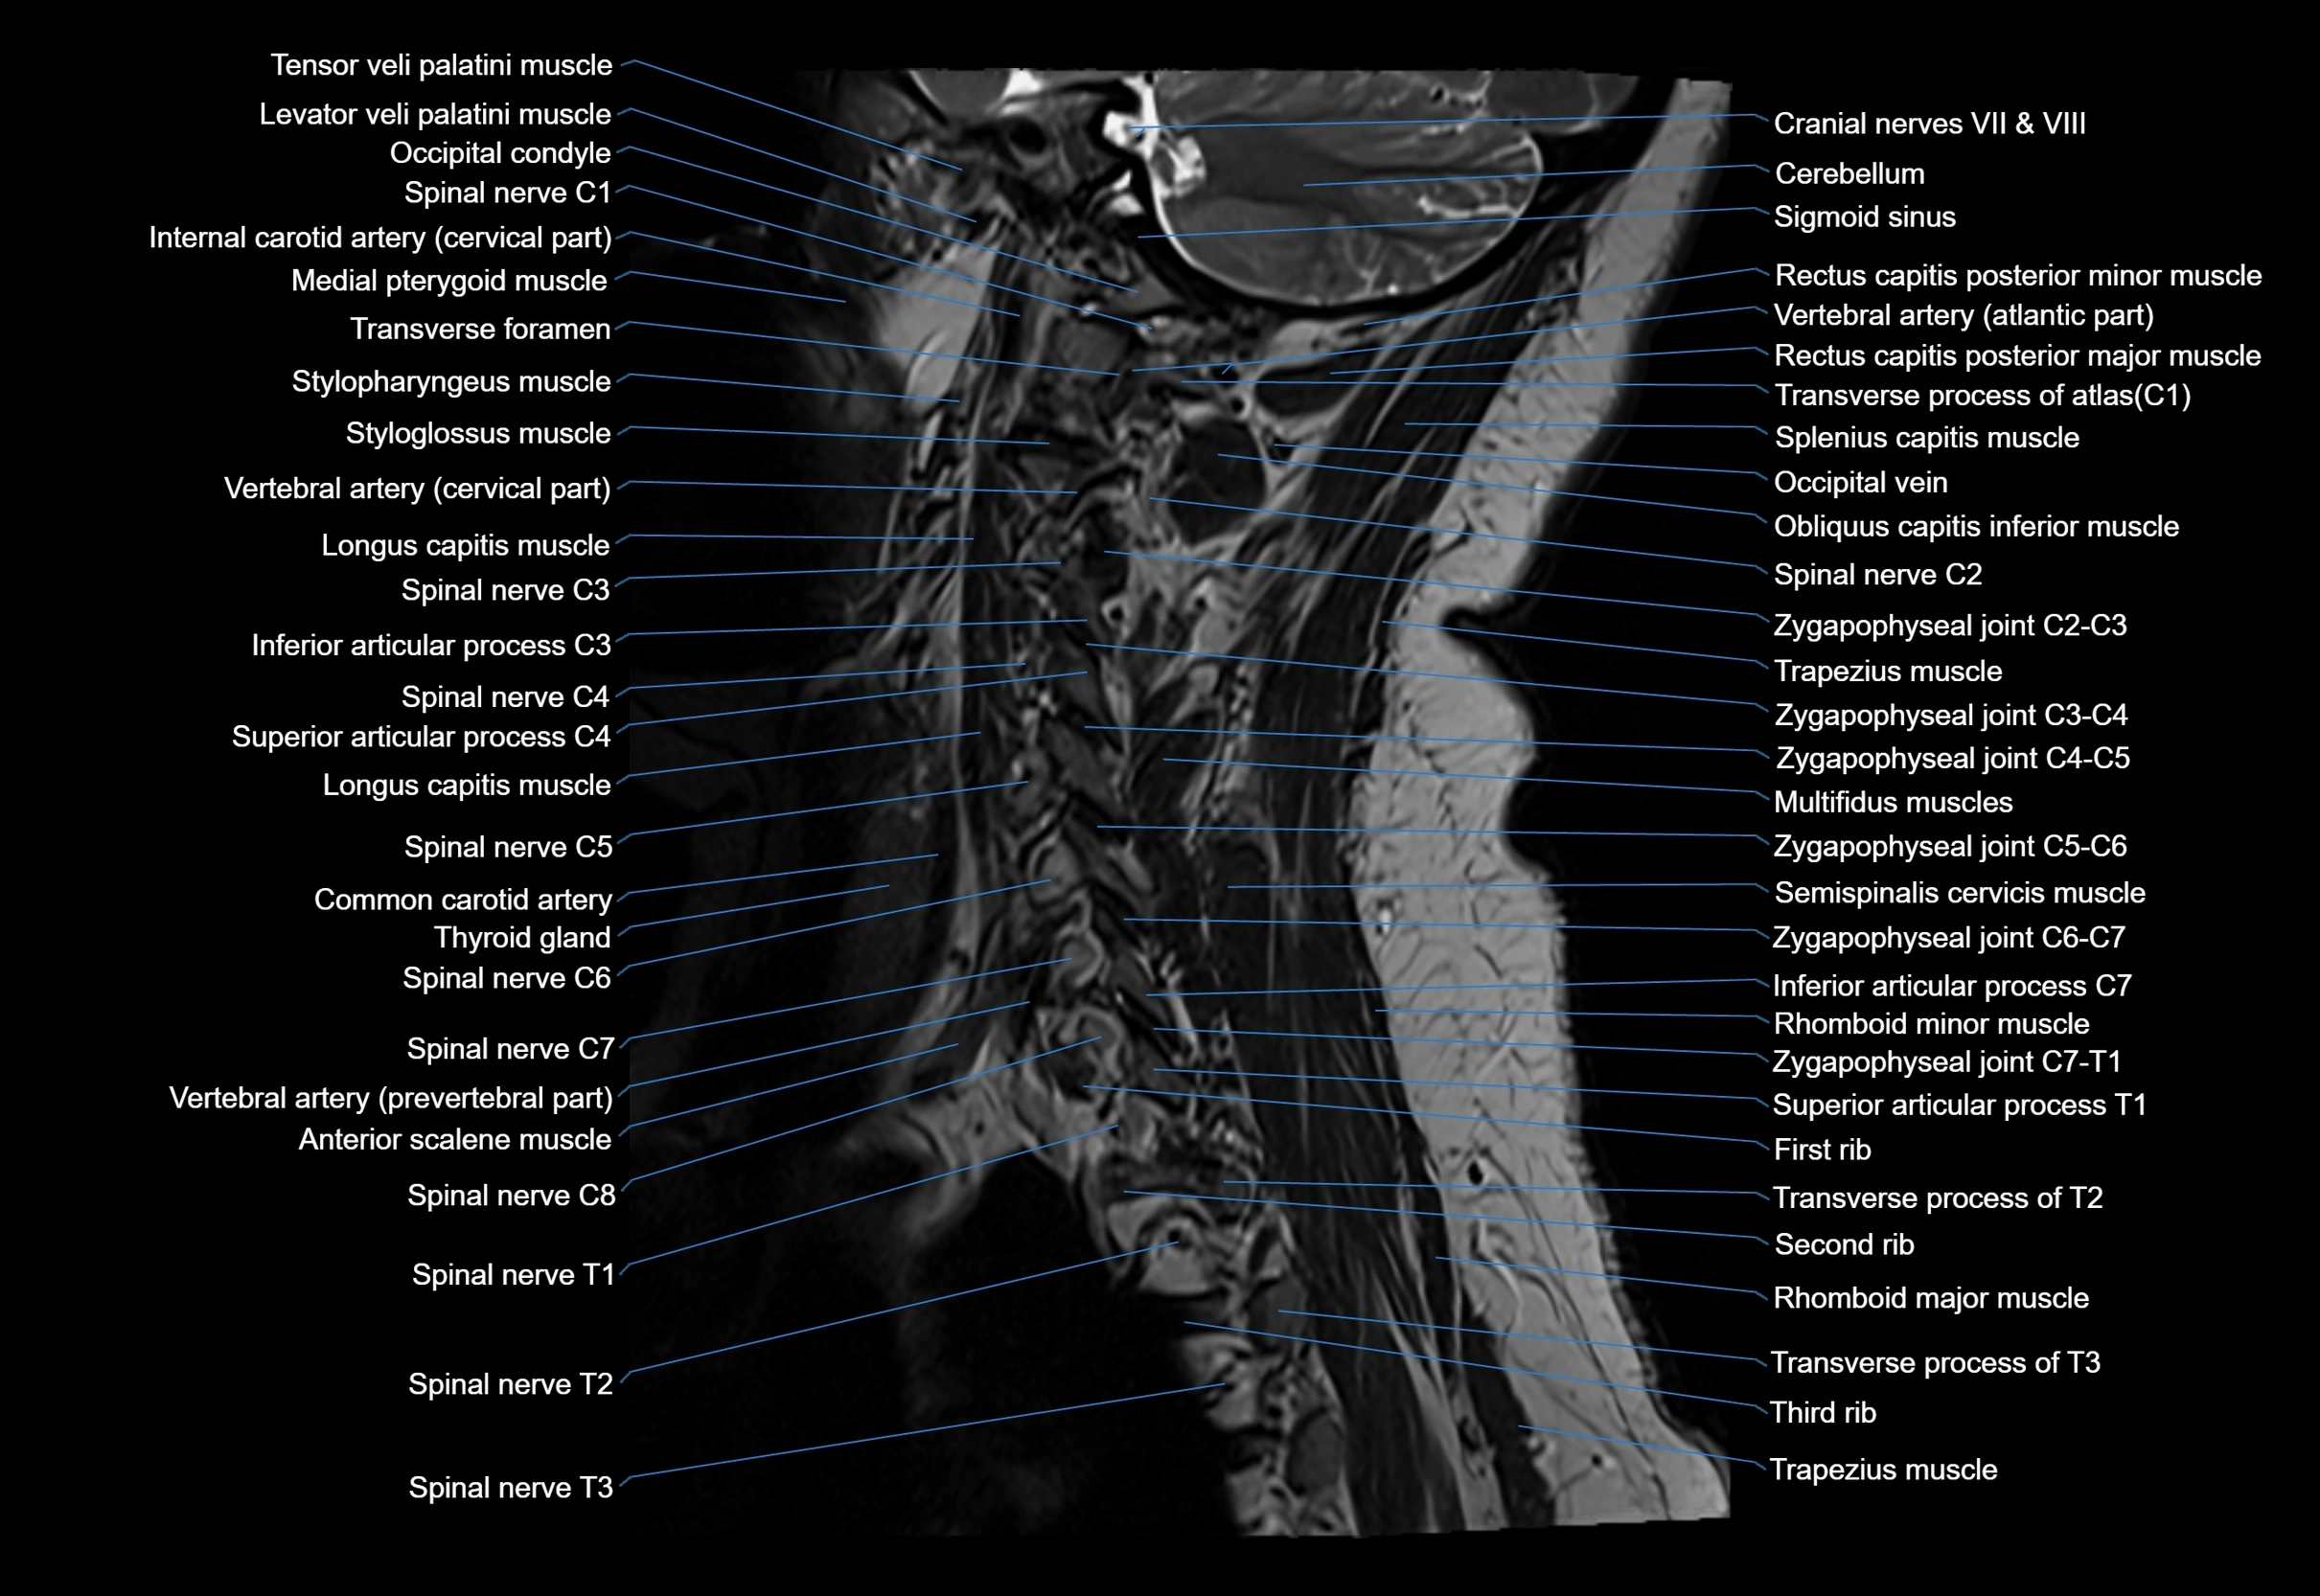

MRI image

image